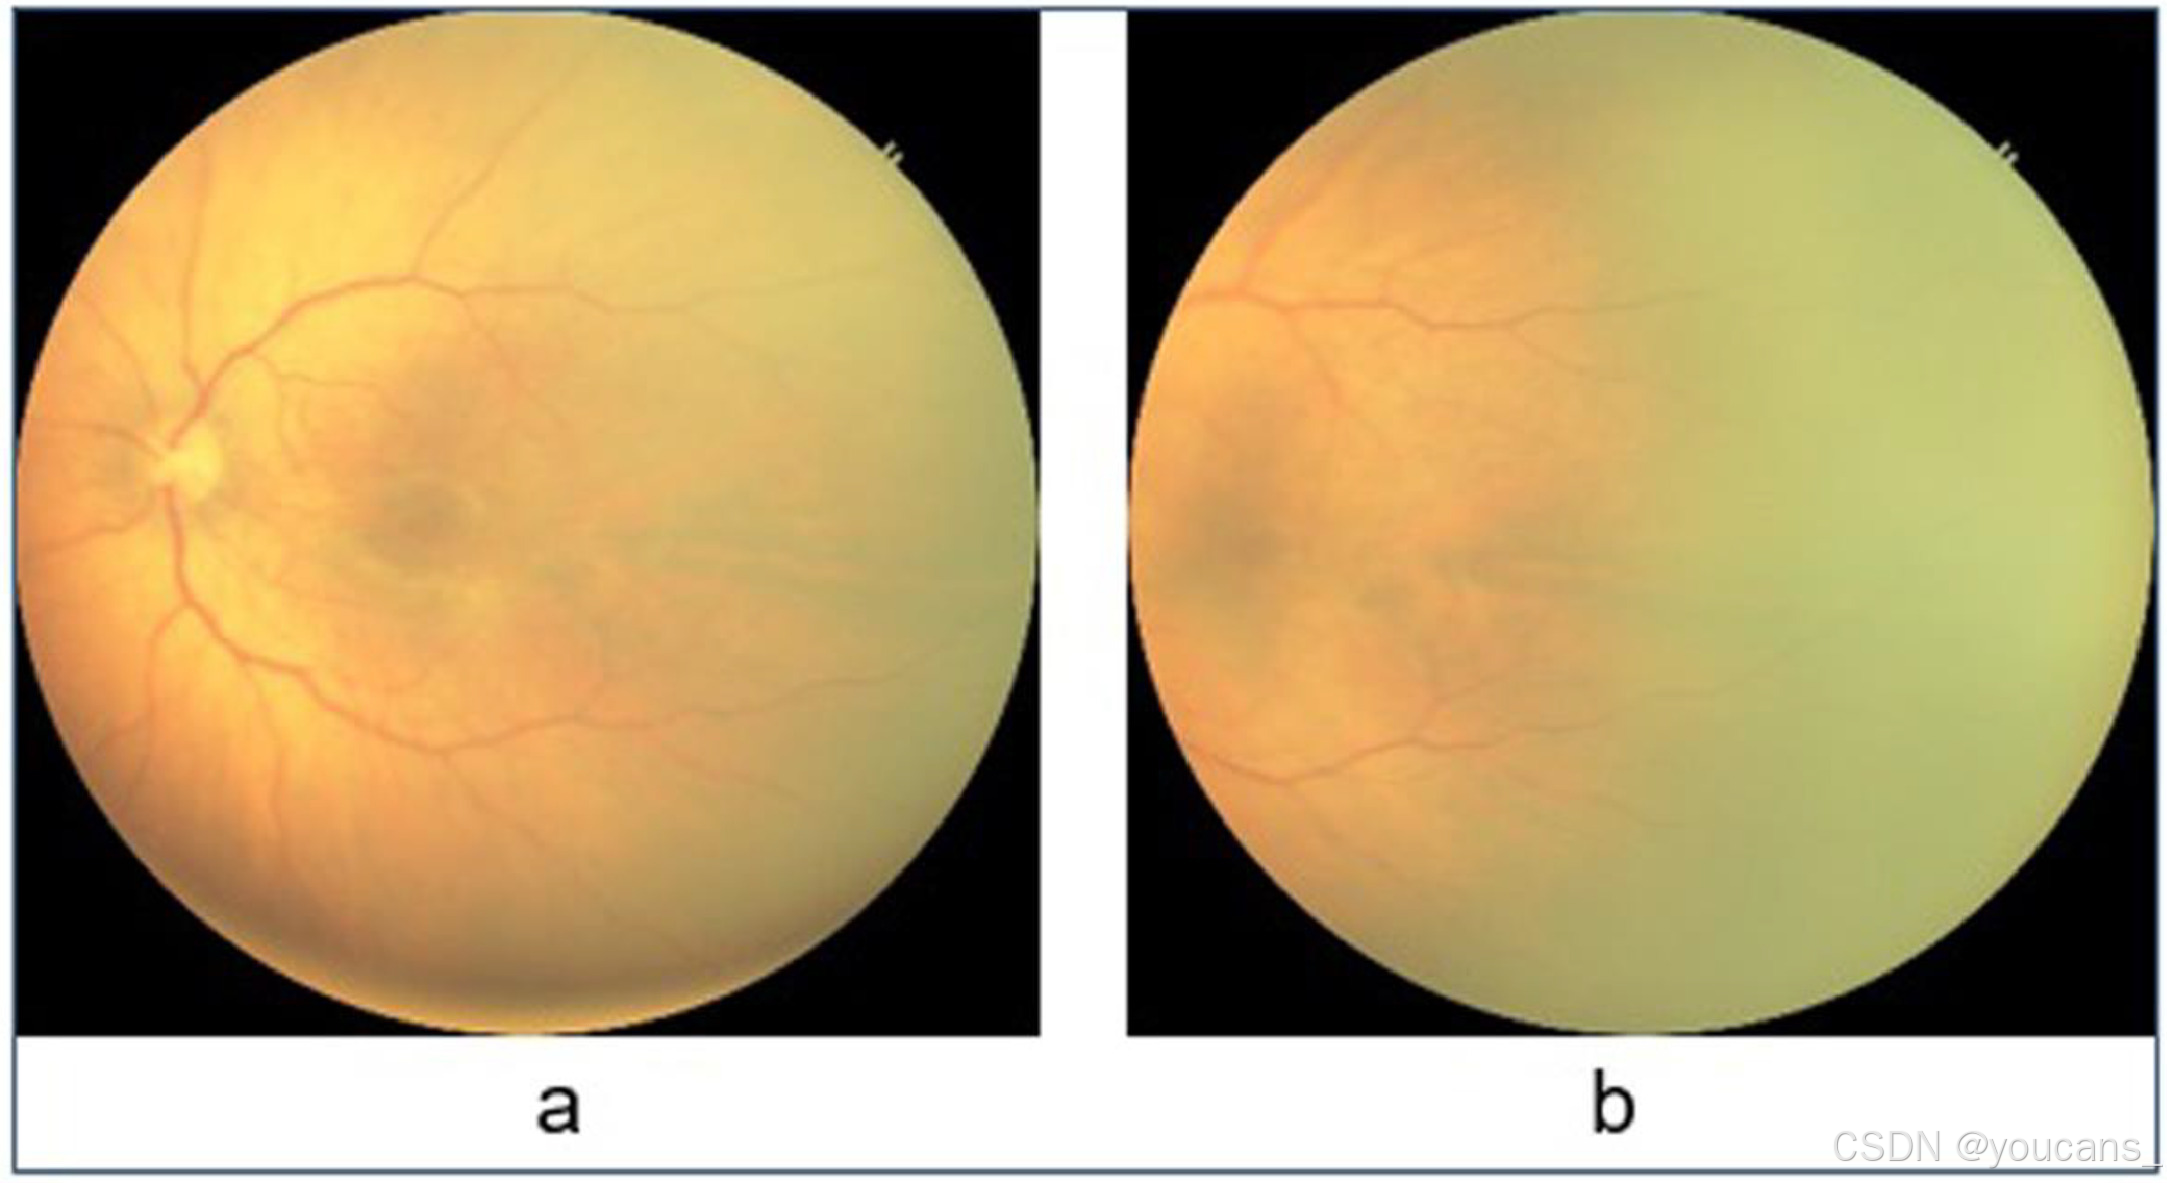

HVDROPDB数据集由早产儿的后部视图和颞部视图的眼底图像组成,如图1 和图2 所示。图1a 和2a 显示了视网膜后部图像(从视网膜的后方拍摄的图像),图1b 和2b 显示了视网膜颞部图像(从视网膜的侧面拍摄的图像)。

图2:Neo 图像(a)后视图,(b)颞部视图。